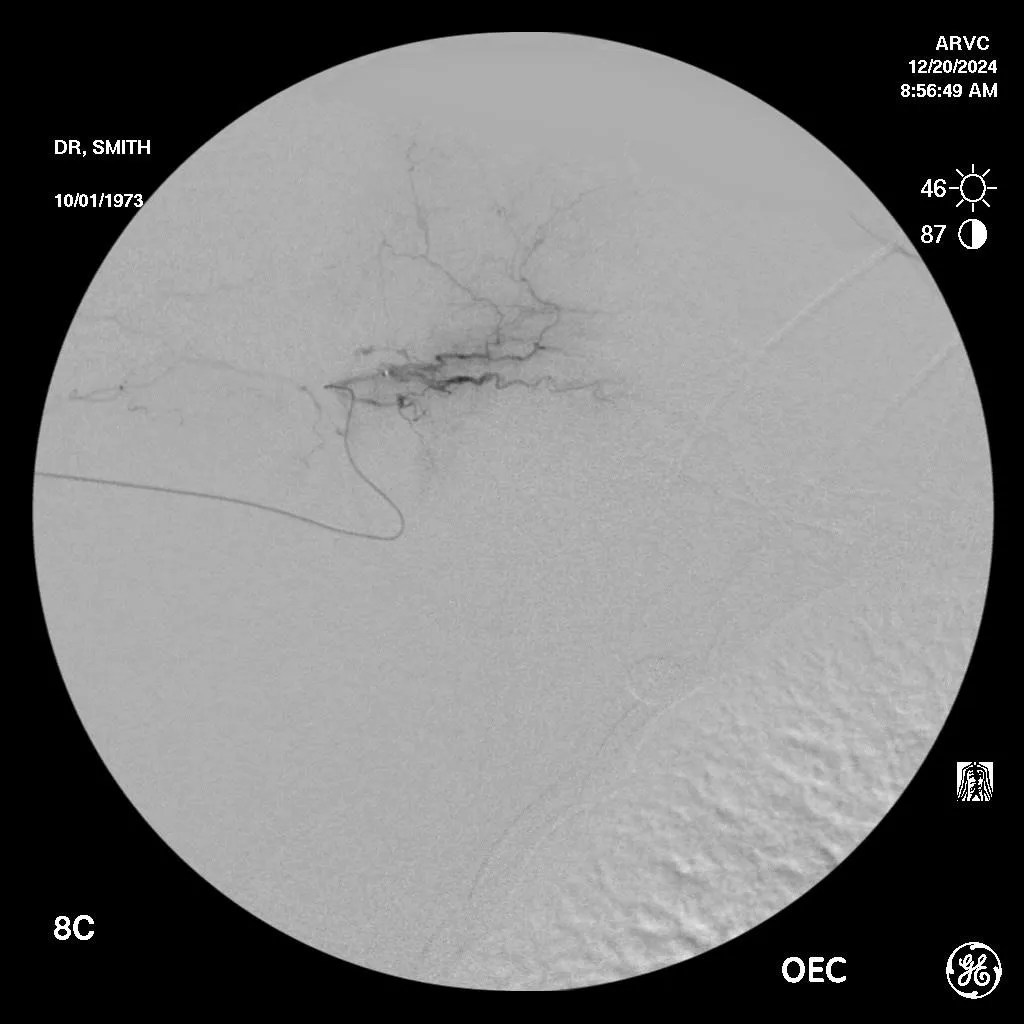

Shaded areas around vessels are called "hyperemia" and are the abnormal growth of micro blood vessels causing pain and inflammation.